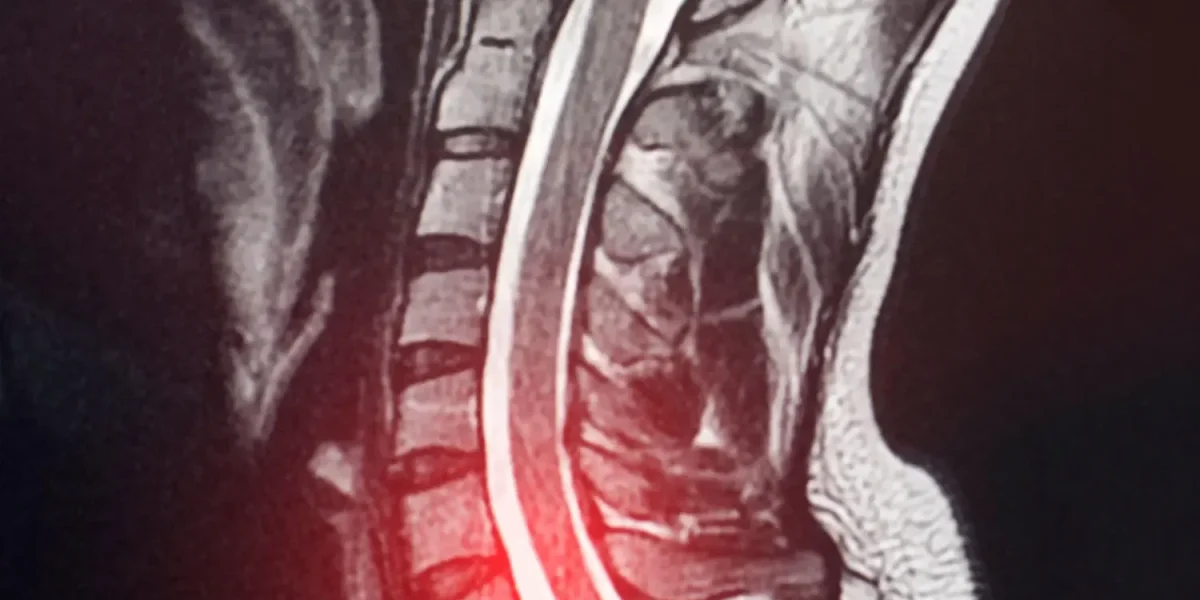

Magnetic Resonance Imaging (MRI): The gold standard for diagnosing cervical disc herniation. MRI provides detailed visualization of soft tissues, including the intervertebral discs, spinal cord, and nerve roots. It can reveal:

- The location and size of the disc herniation

- The degree of neural compression

- Spinal cord changes (if present)

- Other degenerative findings

A 2024 study emphasized that MRI is essential even when X-rays and CT scans appear normal, particularly when neurological symptoms are present (6). Don’t hesitate to request an MRI if your symptoms suggest nerve compression, but initial imaging was negative.